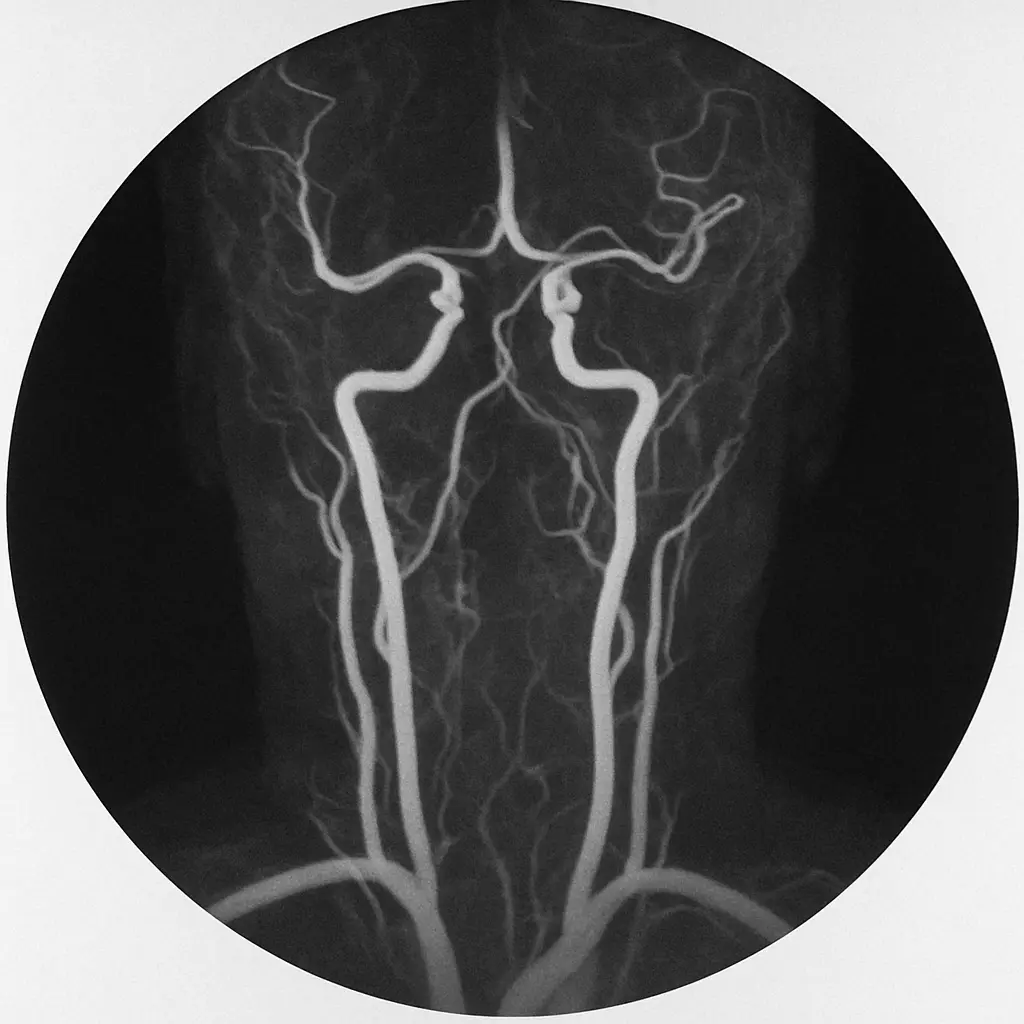

Gadolinium-Based Contrast and Nephrogenic Systemic Fibrosis

The early 2000s brought intense concern over nephrogenic systemic fibrosis (NSF), a debilitating and potentially fatal fibrosing disorder of the skin and internal organs linked to certain gadolinium-based contrast agents (GBCAs). Risk was greatest in patients with advanced CKD (especially those on dialysis) and in those receiving high or repeated doses of less stable linear gadolinium agents. This was a different type of contrast risk in CKD as the organs at risk were not necessarily the kidneys.

Since then, the field has shifted dramatically. Macrocyclic GBCAs—designed with more stable chelation of gadolinium—demonstrate a far lower association with NSF, even in advanced CKD. Current evidence suggests that when these agents are used judiciously, the risk is exceedingly small, though caution and informed consent remain essential.

Patients with eGFR below 30 mL/min/1.73 m² should still undergo careful benefit–risk assessment before GBCA exposure, and dialysis-dependent patients should ideally receive post-procedure hemodialysis to facilitate gadolinium clearance. Yet, as with iodinated contrast, the modern understanding of contrast risk in CKD now supports a more balanced, evidence-based approach rather than absolute avoidance.